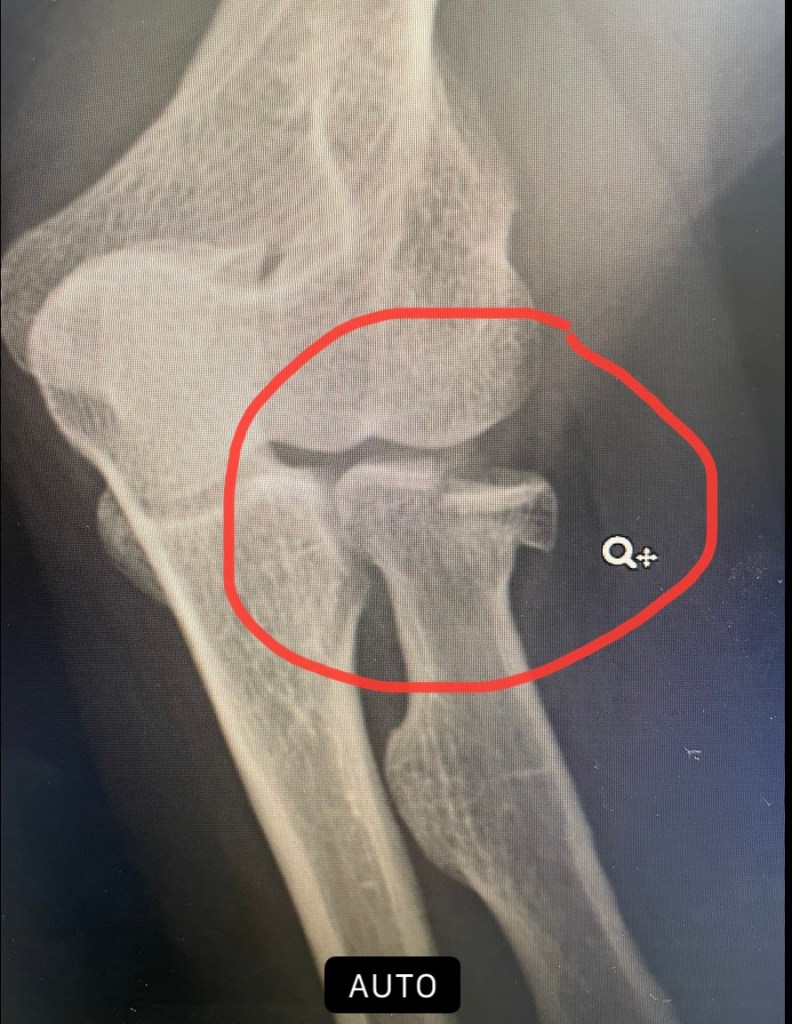

One day, hiking in a lovely county park, I was looking for photos to take, high on coffee, gabbing with Mr. UT, and smack! Tripped over a root and fell flat on my face, dust in my mouth, my cochlear implants flying off! After I quit whimpering, and pulled myself together, I knew something was wrong with my arm.

Sure enough, I found out I had fractured an elbow bone. Good news, no surgery needed! Just wear my brace and physical therapy for 6 weeks.